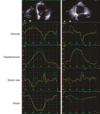

A

Tissue Doppler derived strain and strain rate

Strain Rate

Velocity

Tissue Doppler derived strain and strain rate the one wiht more notorius change is Strain

Strain Tissue Doppler derived strain and strain rate